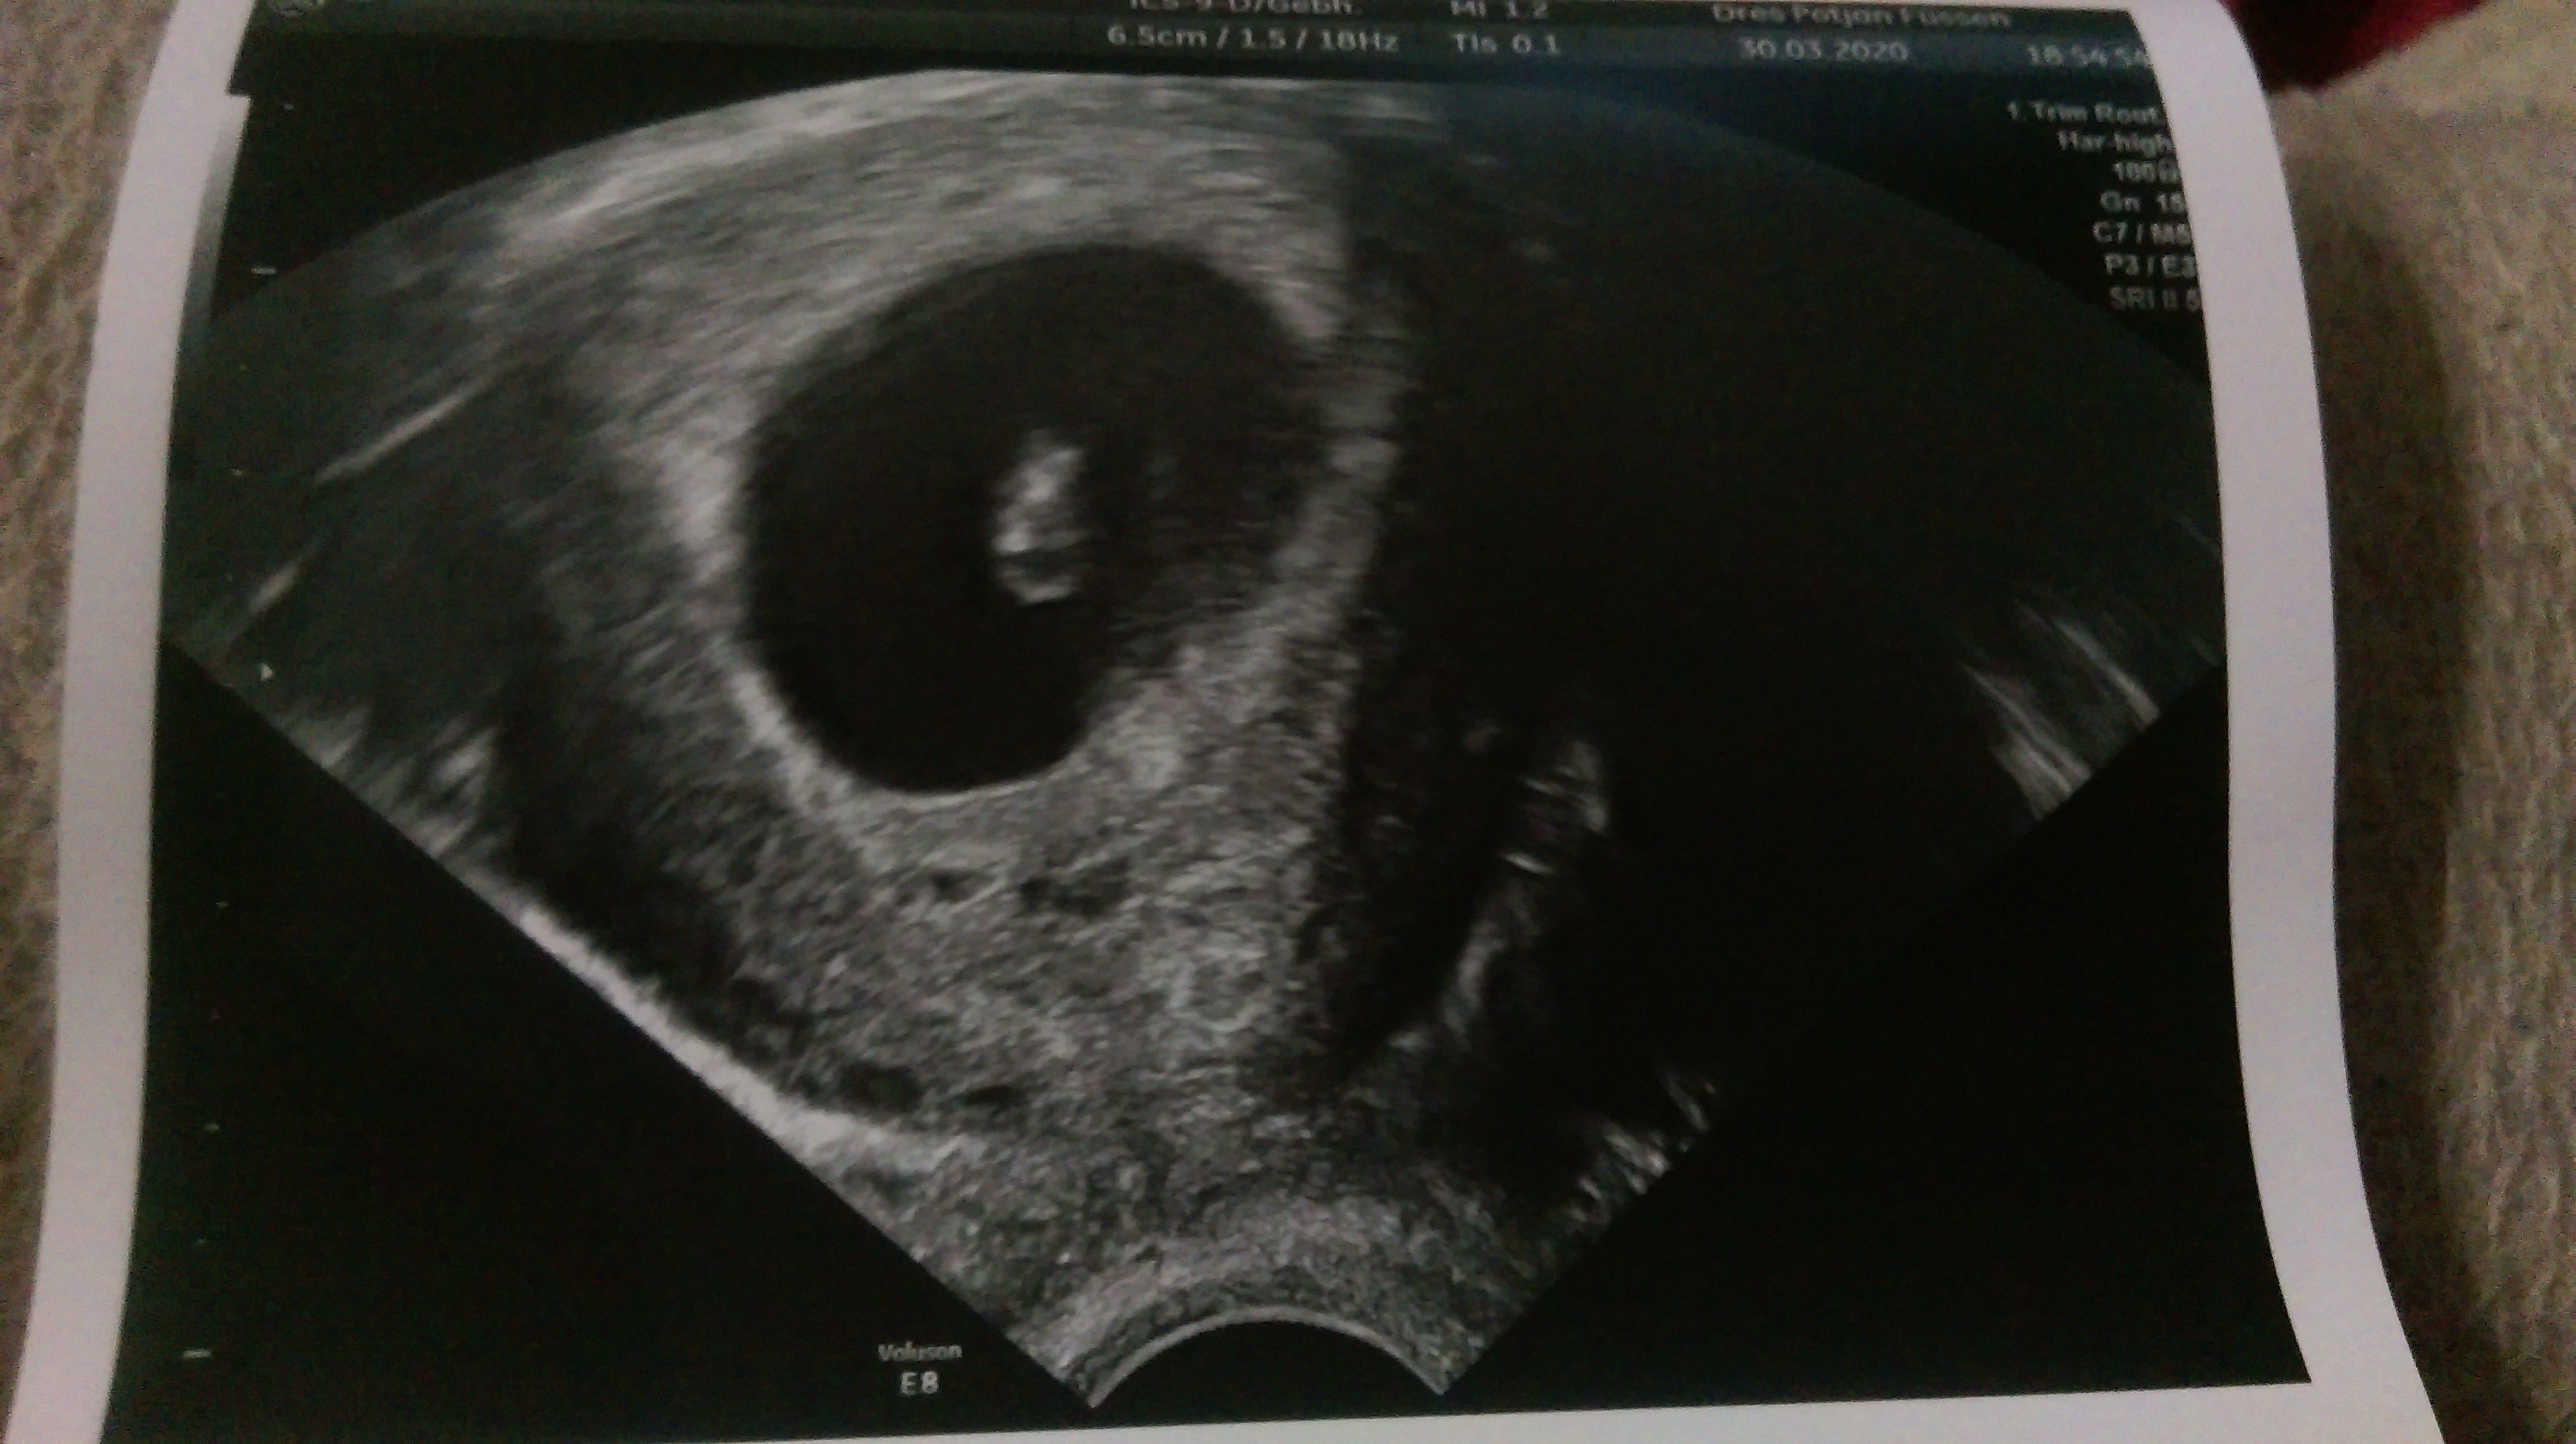

Jak się okazało fasolka dość mocno dokazuje- na usg widziałam jak się rusza [emoji7]

Serduszko bije okolo 160. Fasolka urosła przez 9 dni z 10,3mm do 21,9mm. Tak więc jestem w 8+3 t.c

U mnie jest całkiem duża różnica choć nie powiem Ci ile dni. Byłam w 6 tyg i bylo - CRL 0.56 cm a pecherzyk ciążowy był ponad 2 cm mówił. Jeżeli o to chodziMacie duże róznice w obrazie usg pomiędzy CRL a GS?

Załączniki

Ja miałam na początku mierzone to i to i crl tego dnia było 6t5d a GS 7t2d czyli 3 dni różnicyMacie duże róznice w obrazie usg pomiędzy CRL a GS?